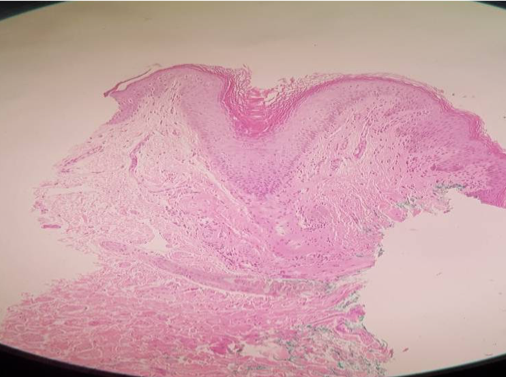

Histology of Biopsies of Labia Majora taken by punch on Patients treated by Endopeel

Anatomo Pathologist